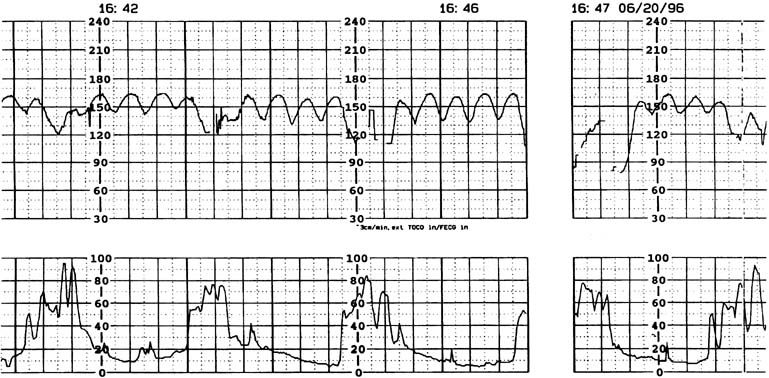

Fig. 4. Intrapartum cardiotocograph tracing (term gestation) in a patient with placental abruption revealing a sinusoidal fetal heart rate pattern just before delivery.

Continuous electronic fetal heart rate monitoring and uterine activity assist the clinician in the assessment of the severity of the abruption. Even if uterine contractions are irregular, their amplitude frequently exceeds that of normal labor, and the baseline tone often is increased. A rapidly enlarging uterus may reflect increasing concealed hemorrhage, which confirms the severity of the separation. Fetal heart rate monitoring may display various abnormalities, including tachycardia, loss of variability, sinusoidal pattern (Fig. 4), pseudosinusoidal pattern,96 or late decelerations. However, a normal heart rate tracing on admission in a patient with suspected abruptio placentae is not a cause for complacency. Rapid deterioration of fetal condition may occur in this situation. This concern cannot be overemphasized.